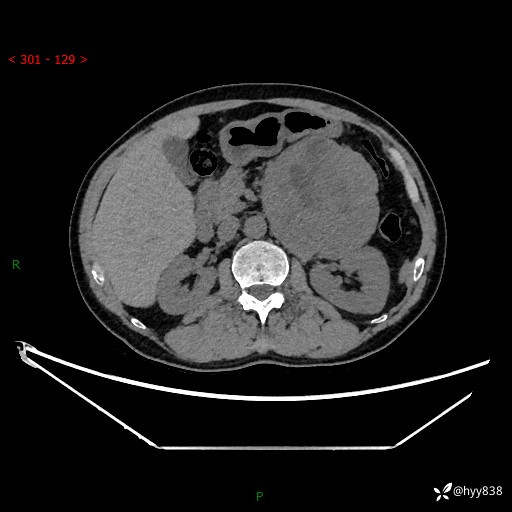

年龄:61岁

主诉:发现腹膜后肿瘤3天

腹部CT平扫+增强(动脉期+静脉期)